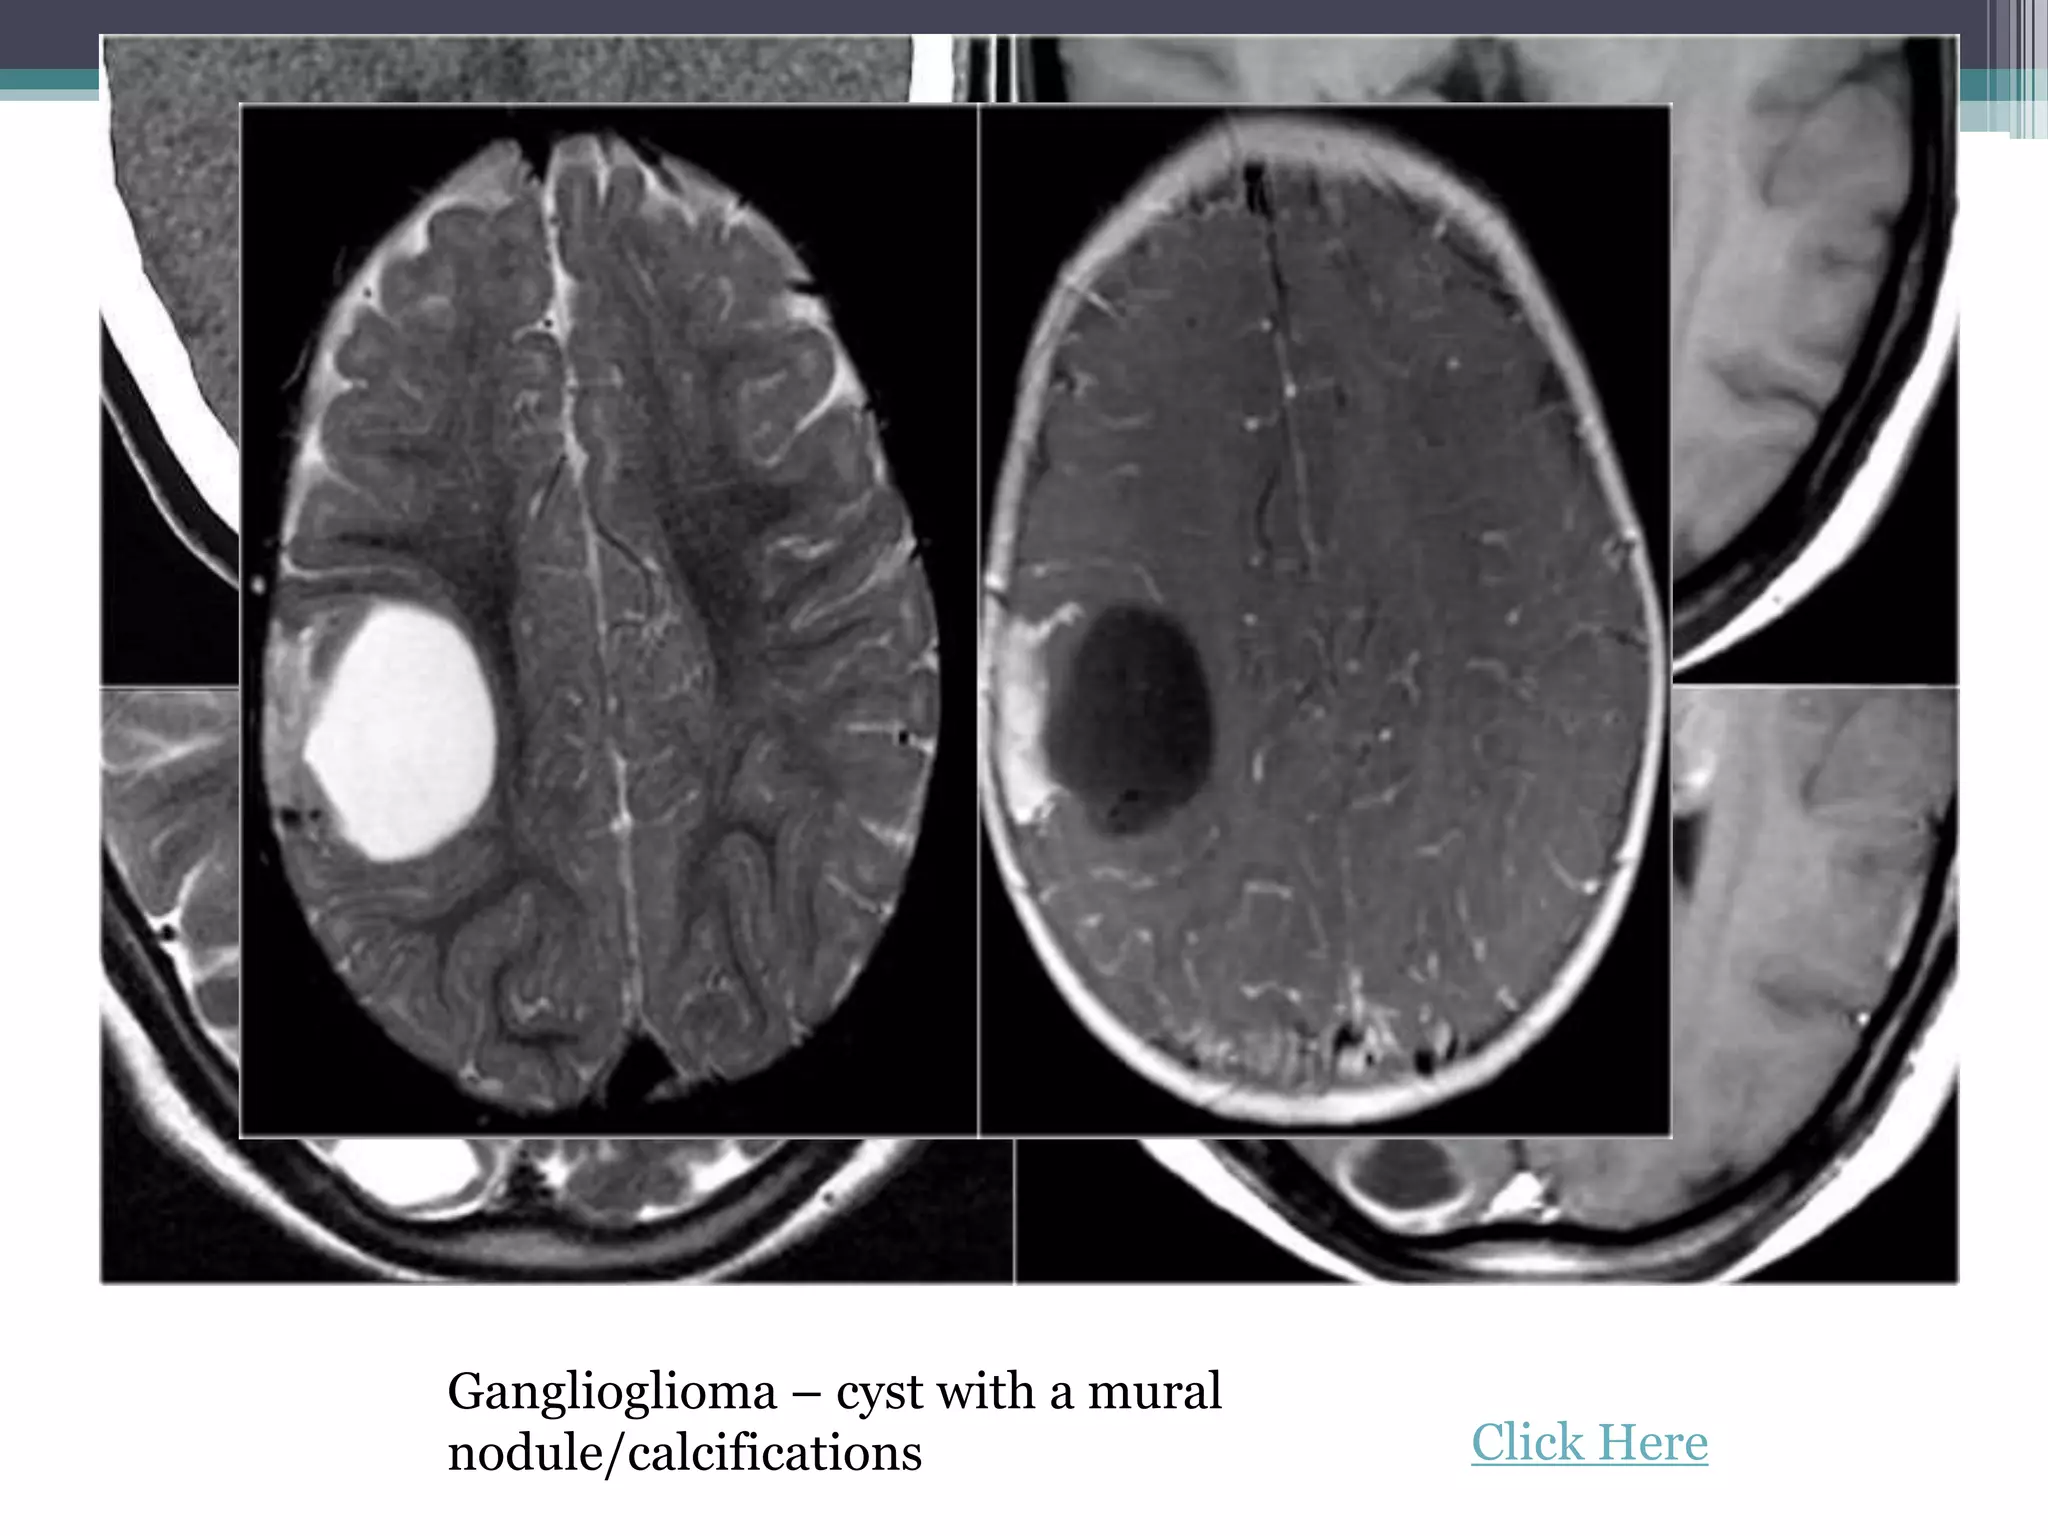

5. Epilepsy associated tumors

• Ganglioglioma

These tumours share the following

characteristics:

•They arise in a cortical location.

•Often located in the temporal lobe.

•Closely related to developmental

malformations.

•Typically seen in adolescents and young

adults.

•Characterized by a benign behaviour, a slow

growth, a sharp delineation and usually show

absence of edema.

•Show signs of chronicity, such as bone

remodeling and scalloping of the adjacent

skull.

Ganglioglioma – cyst with a mural

nodule/calcifications Click Here

Ganglioglioma – cystwith a mural nodule/calcifications Click Here